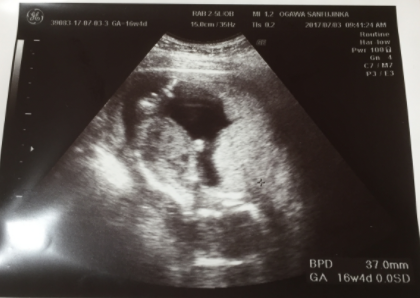

16週3日(16w3d・性別不明)|zzucec さん(28歳)

エコー写真撮影時のエピソード:

16週3日の写真です。前回の健診から4週ぶりの写真でしたが、すごく赤ちゃんが大きくなっていてくれました!もう性別もわかるようでしたが、足が閉じていてわからなくて、少し残念でした。性別がわかれば、色々肌着などのベビーグッズを購入できるのに、もうすこし先まで我慢しておきます!次の健診も4週後!すごく楽しみです!!